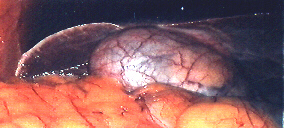

Galloedem.jpg (42318 Byte)

Akute Gallenblasenentzündung leichter und schwerer Form